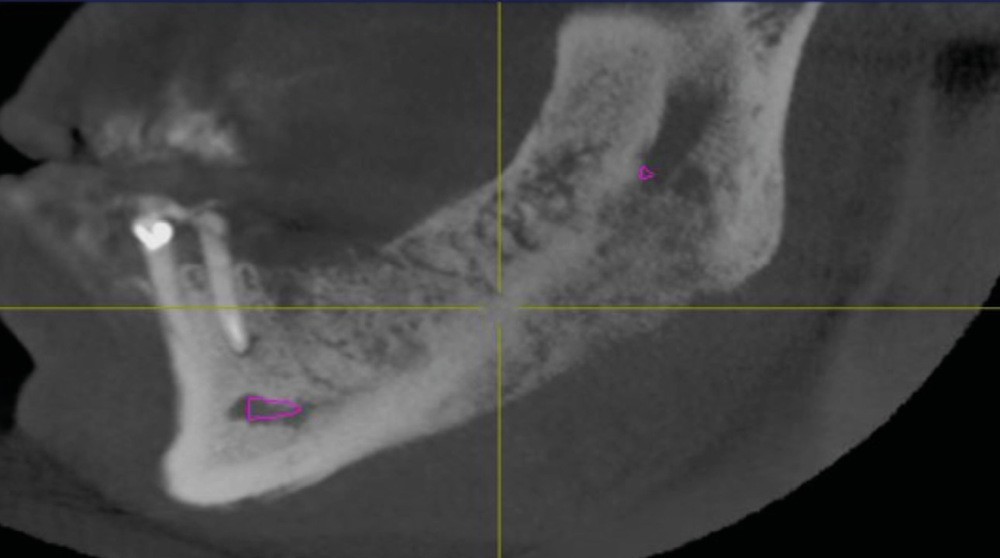

L’examen radiologique (scanner ou tomographie a faisceau conique) est très évocateur. Il montre un épaississement périosté avec « aspect mixte » de l’os médullaire et des « perforations corticales ».

L’ostéomyélite passe par plusieurs stades au cours de son évolution. Au début, les zones d’ostéolyse et de sclérose sont invisibles radiologiquement…